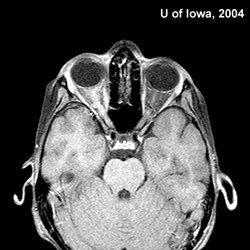

多發性硬化好發於青壯年的中樞神經系統脫髓鞘疾病,遺傳因素對此病的發生有一定的影響。根據不同部分的病灶,出現各異症狀。

多發性硬化是因為自身免疫障礙而導致的中樞神經系統的脫髓鞘性疾病。多在20-40歲之間發病,而在10歲以下和50歲以上發病者很少,起病可急可緩,表現為: